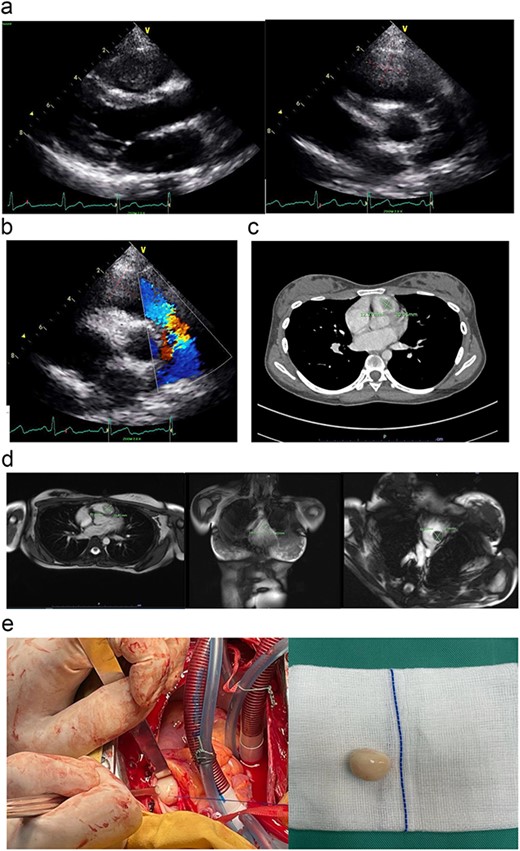

The initial echocardiography (ECHO) assessment findings were consistent with huge vegetation or a mass, obstructing the right ventricular outflow tract (RVOT) and abutting the pulmonary valve leaflet (Fig. 1a). She was initially treated for sterile infective endocarditis for a week duration until she was transferred to our cardiac centre for surgical intervention. After an expert opinion and multi-disciplinary consensus from the cardiologist, and surgeon, the diagnosis of right ventricular (RV) myxoma was confirmed using a multi-modality cardiac imaging such as cardiac computed tomography scan (CT scan) and cardiac magnetic resonance imaging (Fig. 1b–d). The patient was then counselled for surgical intervention.

(a) The parasternal long-axis view of transthoracic ECHO showing a well-defined mass, measuring ~ (2.0 × 2.0 cm) at the right ventricle. (b) The transthoracic ECHO colour flow Doppler showed significant pulmonary valve stenosis with potential Right ventricular outflow tract obstruction caused by the intracardiac mass. (c) The axial cut of a contrast-enhanced computed tomography (CECT) thorax showed a well-defined mass measuring ~ (2 cm × 2 cm) inside the RV. (d) The cardiac magnetic resonance imaging (MRI) confirmed the diagnosis of right RV myxoma by showing a well-defined hypointense mass measuring ~ (1.7 × 2.0 cm). (e) The tumour was identified and excised via a median sternotomy, bicaval cannulation, cardiopulmonary bypass, hypothermia, and cardiac arrested via antegrade cold-blood cardioplegia. The tumour was excised via a pulmonary arteriotomy approach. The tumour is well-defined, firm in consistency, and smooth surface. The size is ~ (2 cm × 2 cm).